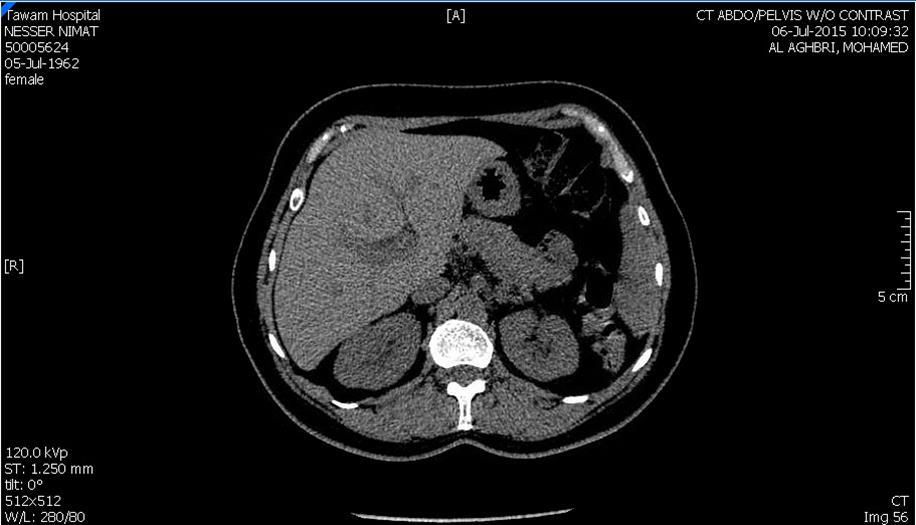

Blood tests on April 14th showed: Na = 131, K = 5.1, Urea = 6.9, S. Creatinine = 96, and eGFR = 61ml/min. Urine analysis and cultures confirmed E. coli urosepsis, blood cultures were negative. Renal US revealed echogenic kidneys, mild bilateral hydronephrosis of about 12 mm with normal ureters and urinary bladder (Figure 1 and Figure 2). Treatment with oral antibiotics resulted in improvement of temperature and dysuria. On April 20th patient seen by endocrinology and nephrology because of persistent back pain, dapagliflozin was discontinued and followed by resolution of symptoms in few days. Patient had two kidney ultrasounds in May and June, both indicated gradual resolution of bilateral hydronephrosis. Repeat CT of the abdomen on July 7th revealed complete resolution of hydronephrosis (Figure 3). Most recent eGFR is 72 ml/min.

Figure 1.Right kidney hydronephrosis

Right kidney hydronephrosis